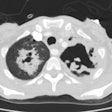

CXR demonstrates migratory infiltrates, but after 1 to 2 months the lesions become stable nodules or cysts predominantly in the lower lobes. Pleural effusions can be seen.CT findings include poorly marginated peripheral or subpleural nodules measuring approximately 2cm (up to 74% of cases) with surrounding ground-glass and a streaky opacity connecting the nodule to the pleural surface [3], pleural effusion, hydropneumothorax, airspace consolidation, and thin walled cysts [1,2].